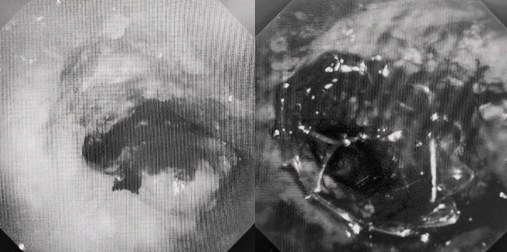

時(shí)間就是生命!了解患者病情后,歐陽海峰立刻啟動(dòng)氣道梗阻緊急救治通道,協(xié)調(diào)院前轉(zhuǎn)運(yùn),急診快速入院流程。凌晨患者入院胸部CT顯示,現(xiàn)存唯一的呼吸通道在右主支氣管處,狹窄處僅約3毫米,患者命懸一線!

患者入院第二天,在麻醉手術(shù)中心全力配合下,歐陽海峰帶領(lǐng)呼吸介入團(tuán)隊(duì),歷時(shí)40分鐘快速置入硬質(zhì)支氣管鏡、鏟切腫瘤,并順利植入全覆膜TTS支氣管金屬支架?;颊邭舛贪Y狀即刻緩解,為患者贏得了寶貴的后續(xù)治療機(jī)會(huì)。